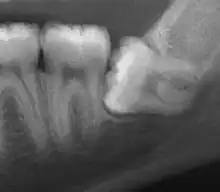

| Impacted wisdom tooth with a horizontal orientation | |

| Diagnostic method | X-rays, CT scans |

Diagnosis of ectopic teeth typically involves a comprehensive dental examination, including X-rays and other imaging tests. Treatment options for ectopic teeth depend on the location and severity of the condition, as well as the age and overall health of the patient. In some cases, observation and monitoring may be sufficient, while in other cases, surgical intervention may be necessary to remove the ectopic tooth and prevent further complications.[5]